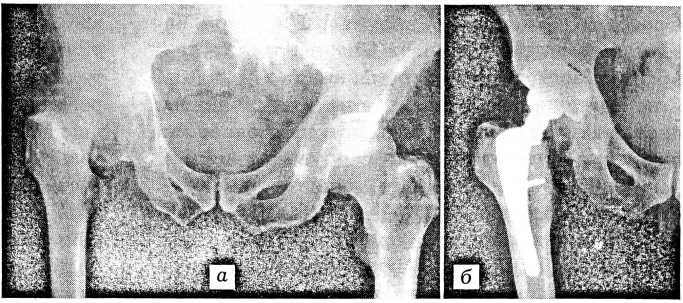

В рамках сотрудничества с немецкой фирмой «ESKA medical Lubeck» 15 больным произведены операции с использованием оригинального по конструкции эндопротеза этой фирмы (рис. 2). Его поверхность структурирована комохромовым литьем, благодаря чему имплантаты надежно удерживаются во впадине и бедре без дополнительной фиксации.

Рис. 2. Рентгенограммы больного Д. с правосторонним диспластическим коксартрозом.

а — до операции; б — после тотального эндопротезирования протезом «ESKA medical».